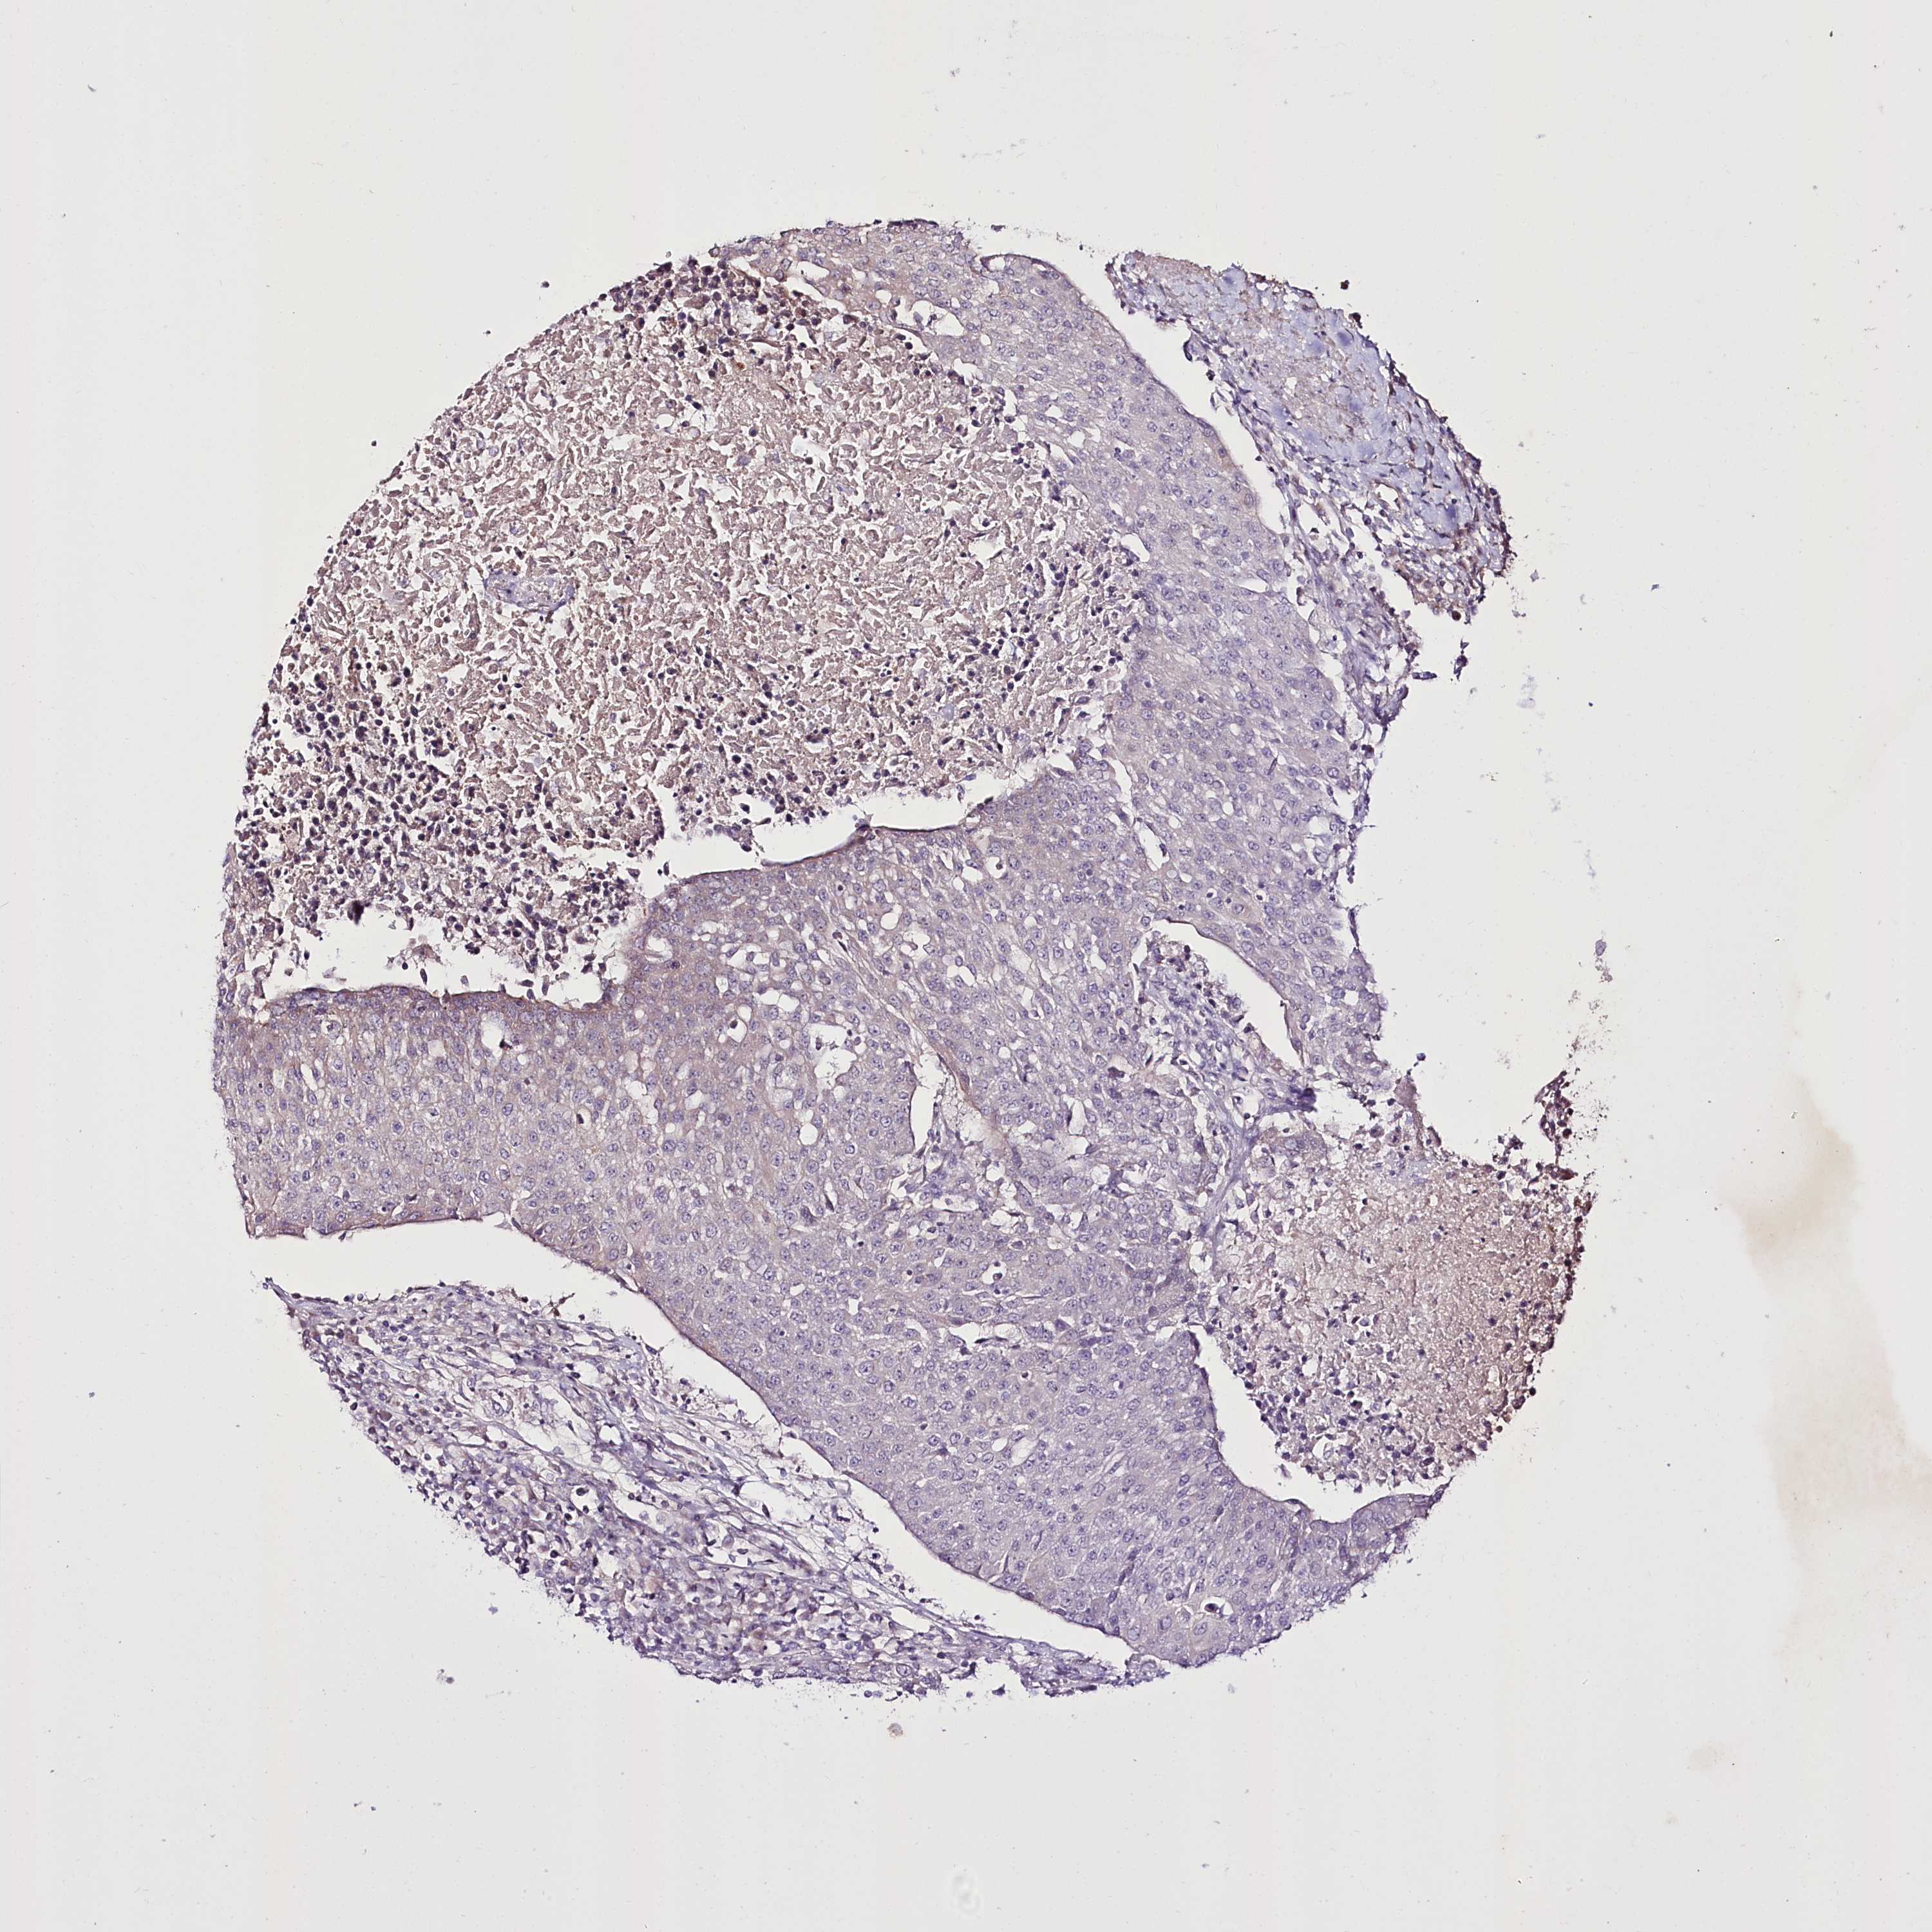

UROTHELIAL CANCER - Protein expressioni

A mouse-over function shows sample information and annotation data. Click on an image to view it in a full screen mode. Samples can be filtered based on level of antibody staining by selecting one or several of the following categories: high, medium, low and not detected. The assay and annotation is described here.

Note that samples used for immunohistochemistry by the Human Protein Atlas do not correspond to samples in the TCGA dataset.

Antibody stainingi

Antibody staining in the annotated cell types in the current human tissue is reported as not detected, low, medium, or high, based on conventional immunohistochemistry profiling in selected tissues. This score is based on the combination of the staining intensity and fraction of stained cells.

Each image is clickable and will lead to virtual microscopy that enables deeper exploration of all samples and also displays staining intensity scores, fraction scores and subcellular localization as well as patient and tissue information for each sample.

Antibody HPA038450

Antibody HPA038451

Staining

High

Medium

Low

Not detected

Intensity

Strong

Moderate

Weak

Negative

Quantity

>75%

75%-25%

<25%

None

Location

Nuclear

Cytoplasmic/membranous

Cytoplasmic/membranous,nuclear

Urothelial carcinoma, High grade

Urothelial carcinoma, Low grade

Urothelial carcinoma, NOS